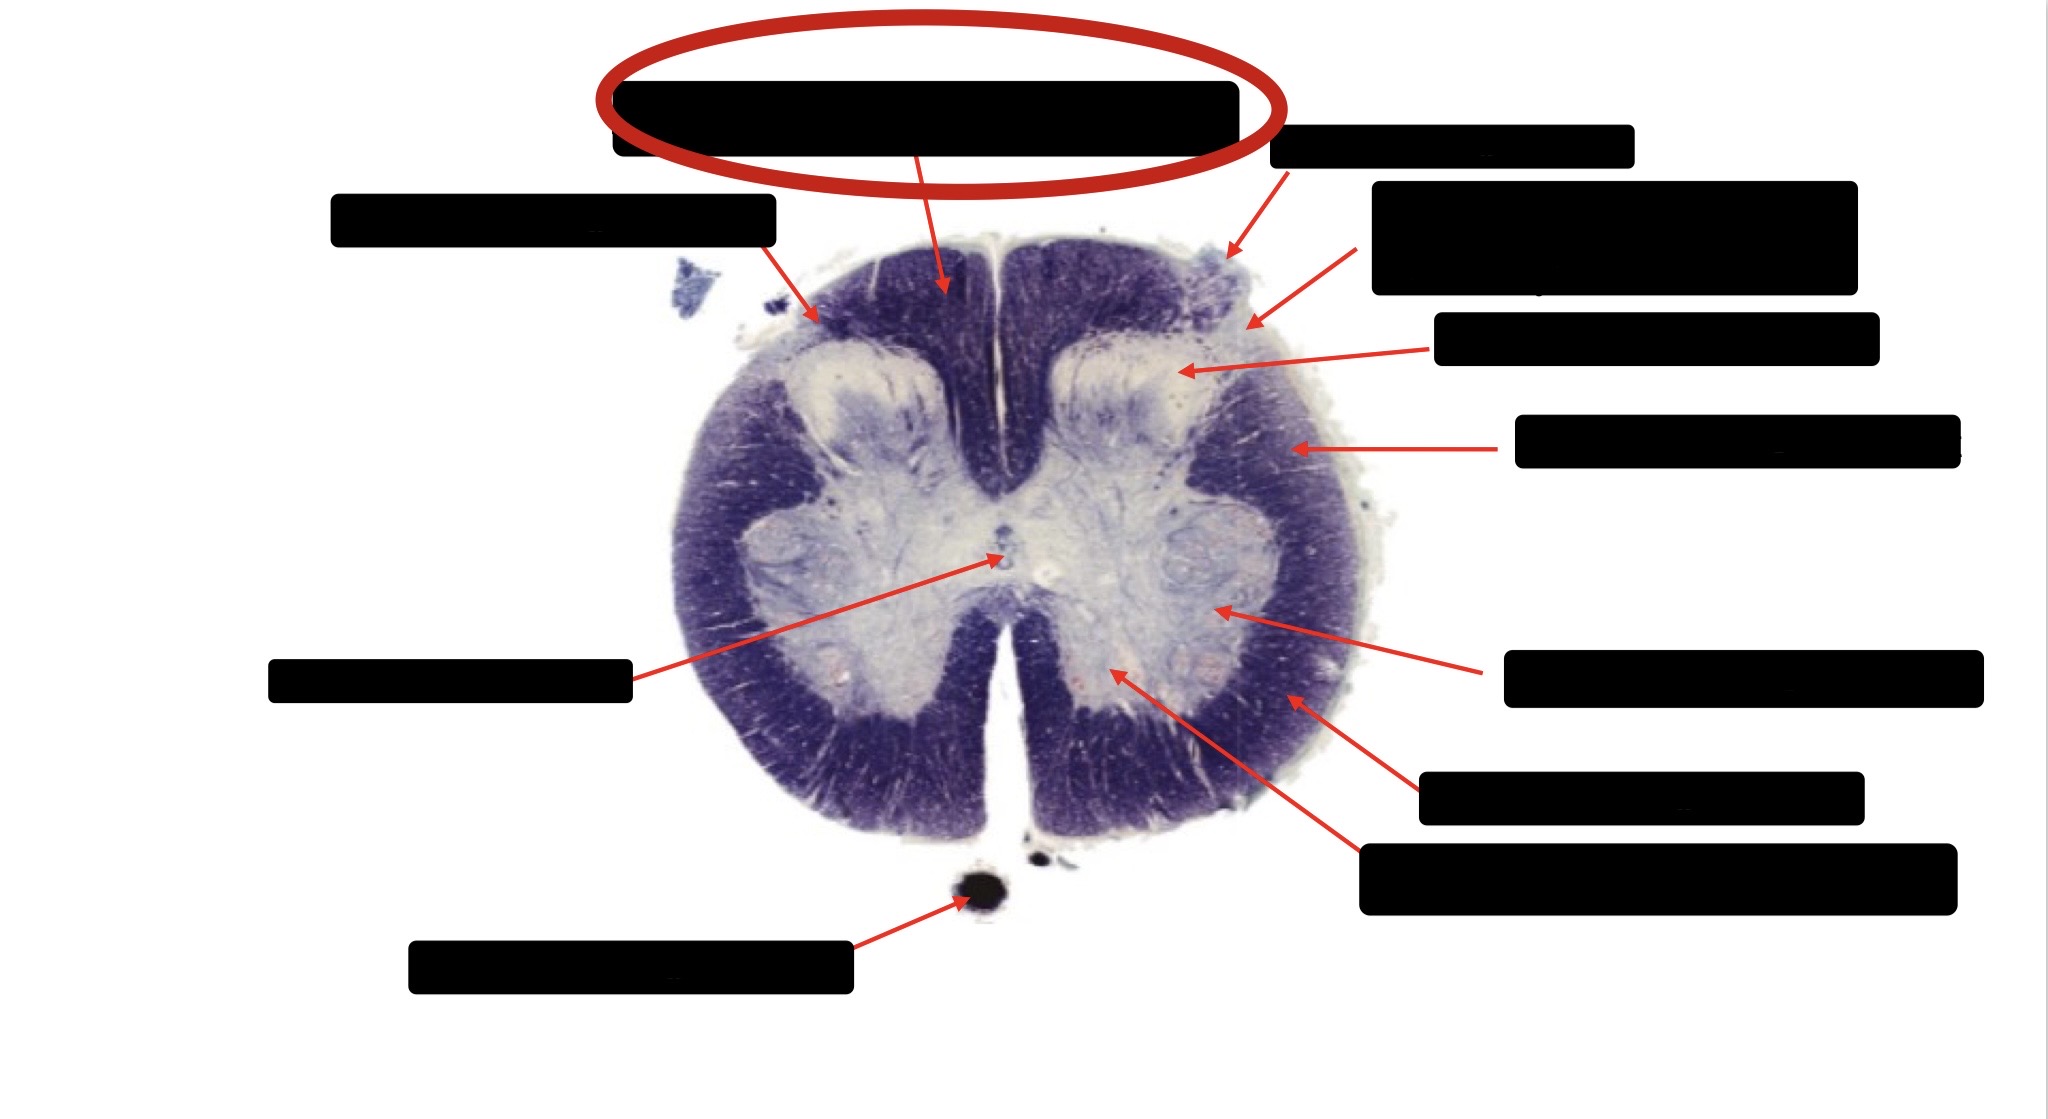

Anterior Spinal Artery

Denticulate Ligament

Ventral Root

Dorsal Root

Posterior Column Fasciculus Gracilis

Large Fiber Entry Zone

Central Canal

Dorsal Rootlet

Lissaeur’s Tract & Small Fiber Entry Zone

Substantia Gelatinosa

Lateral Corticospinal Tract

Anterior Horn Motor Neuron

Spinothalmic Tract